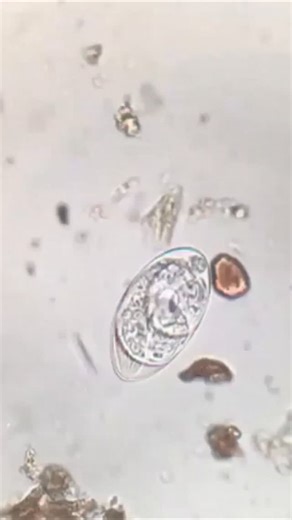

Strongyloides stercoralis (3rd stage larva) - Dog

Hookworm(Ancyclostoma) Rhabditiform larvae Canine

larva de strongyloides stercoralis

Strongyloides stercoralis rhabditiform larvae

Strongyloides stercoralis Photo Compilation (Medtech Study Guide)

Understanding Strongyloides Rhabditiform Larvae: A Comprehe

Strongyloides stercoralis under microscope (in Stool sample)